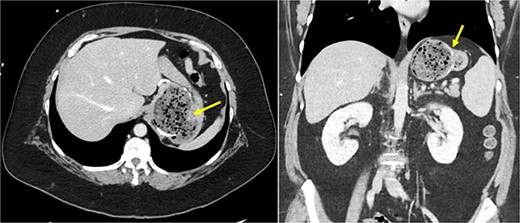

She underwent a CT of her abdomen and pelvis that showed concern for a possible gastrogastric fistula (Fig. 1) that was confirmed via an upper GI series demonstrating the passage of oral contrast into the remnant stomach (Fig. 2). Subsequent esophagogastroduodenoscopy (EGD) also revealed an ulcer at the site of the GGF (Fig. 3). The patient was discharged home on Omeprazole twice daily. She was seen in the outpatient setting with bariatric surgery and scheduled in 3 months for laparoscopic take-down of her gastrogastric fistula.

Cross-sectional CT imaging demonstrating concern for gastrogastric fistula.